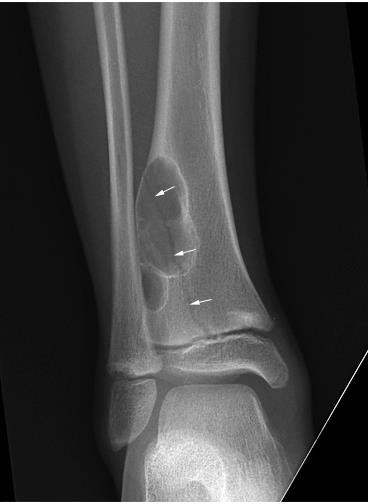

- X quang:

- Cho phép chẩn đoán xác định gãy xương

- Xác định kiểu gãy: đơn giản (gãy ngang, gãy chéo xoắn…), phức tạp (gãy nhiều tầng, nhiều mảnh…), xuyên khớp.

Hình : Các loại gãy xương thường gặp

(ngang, xoắn, chéo, nhiều mảnh, rời)